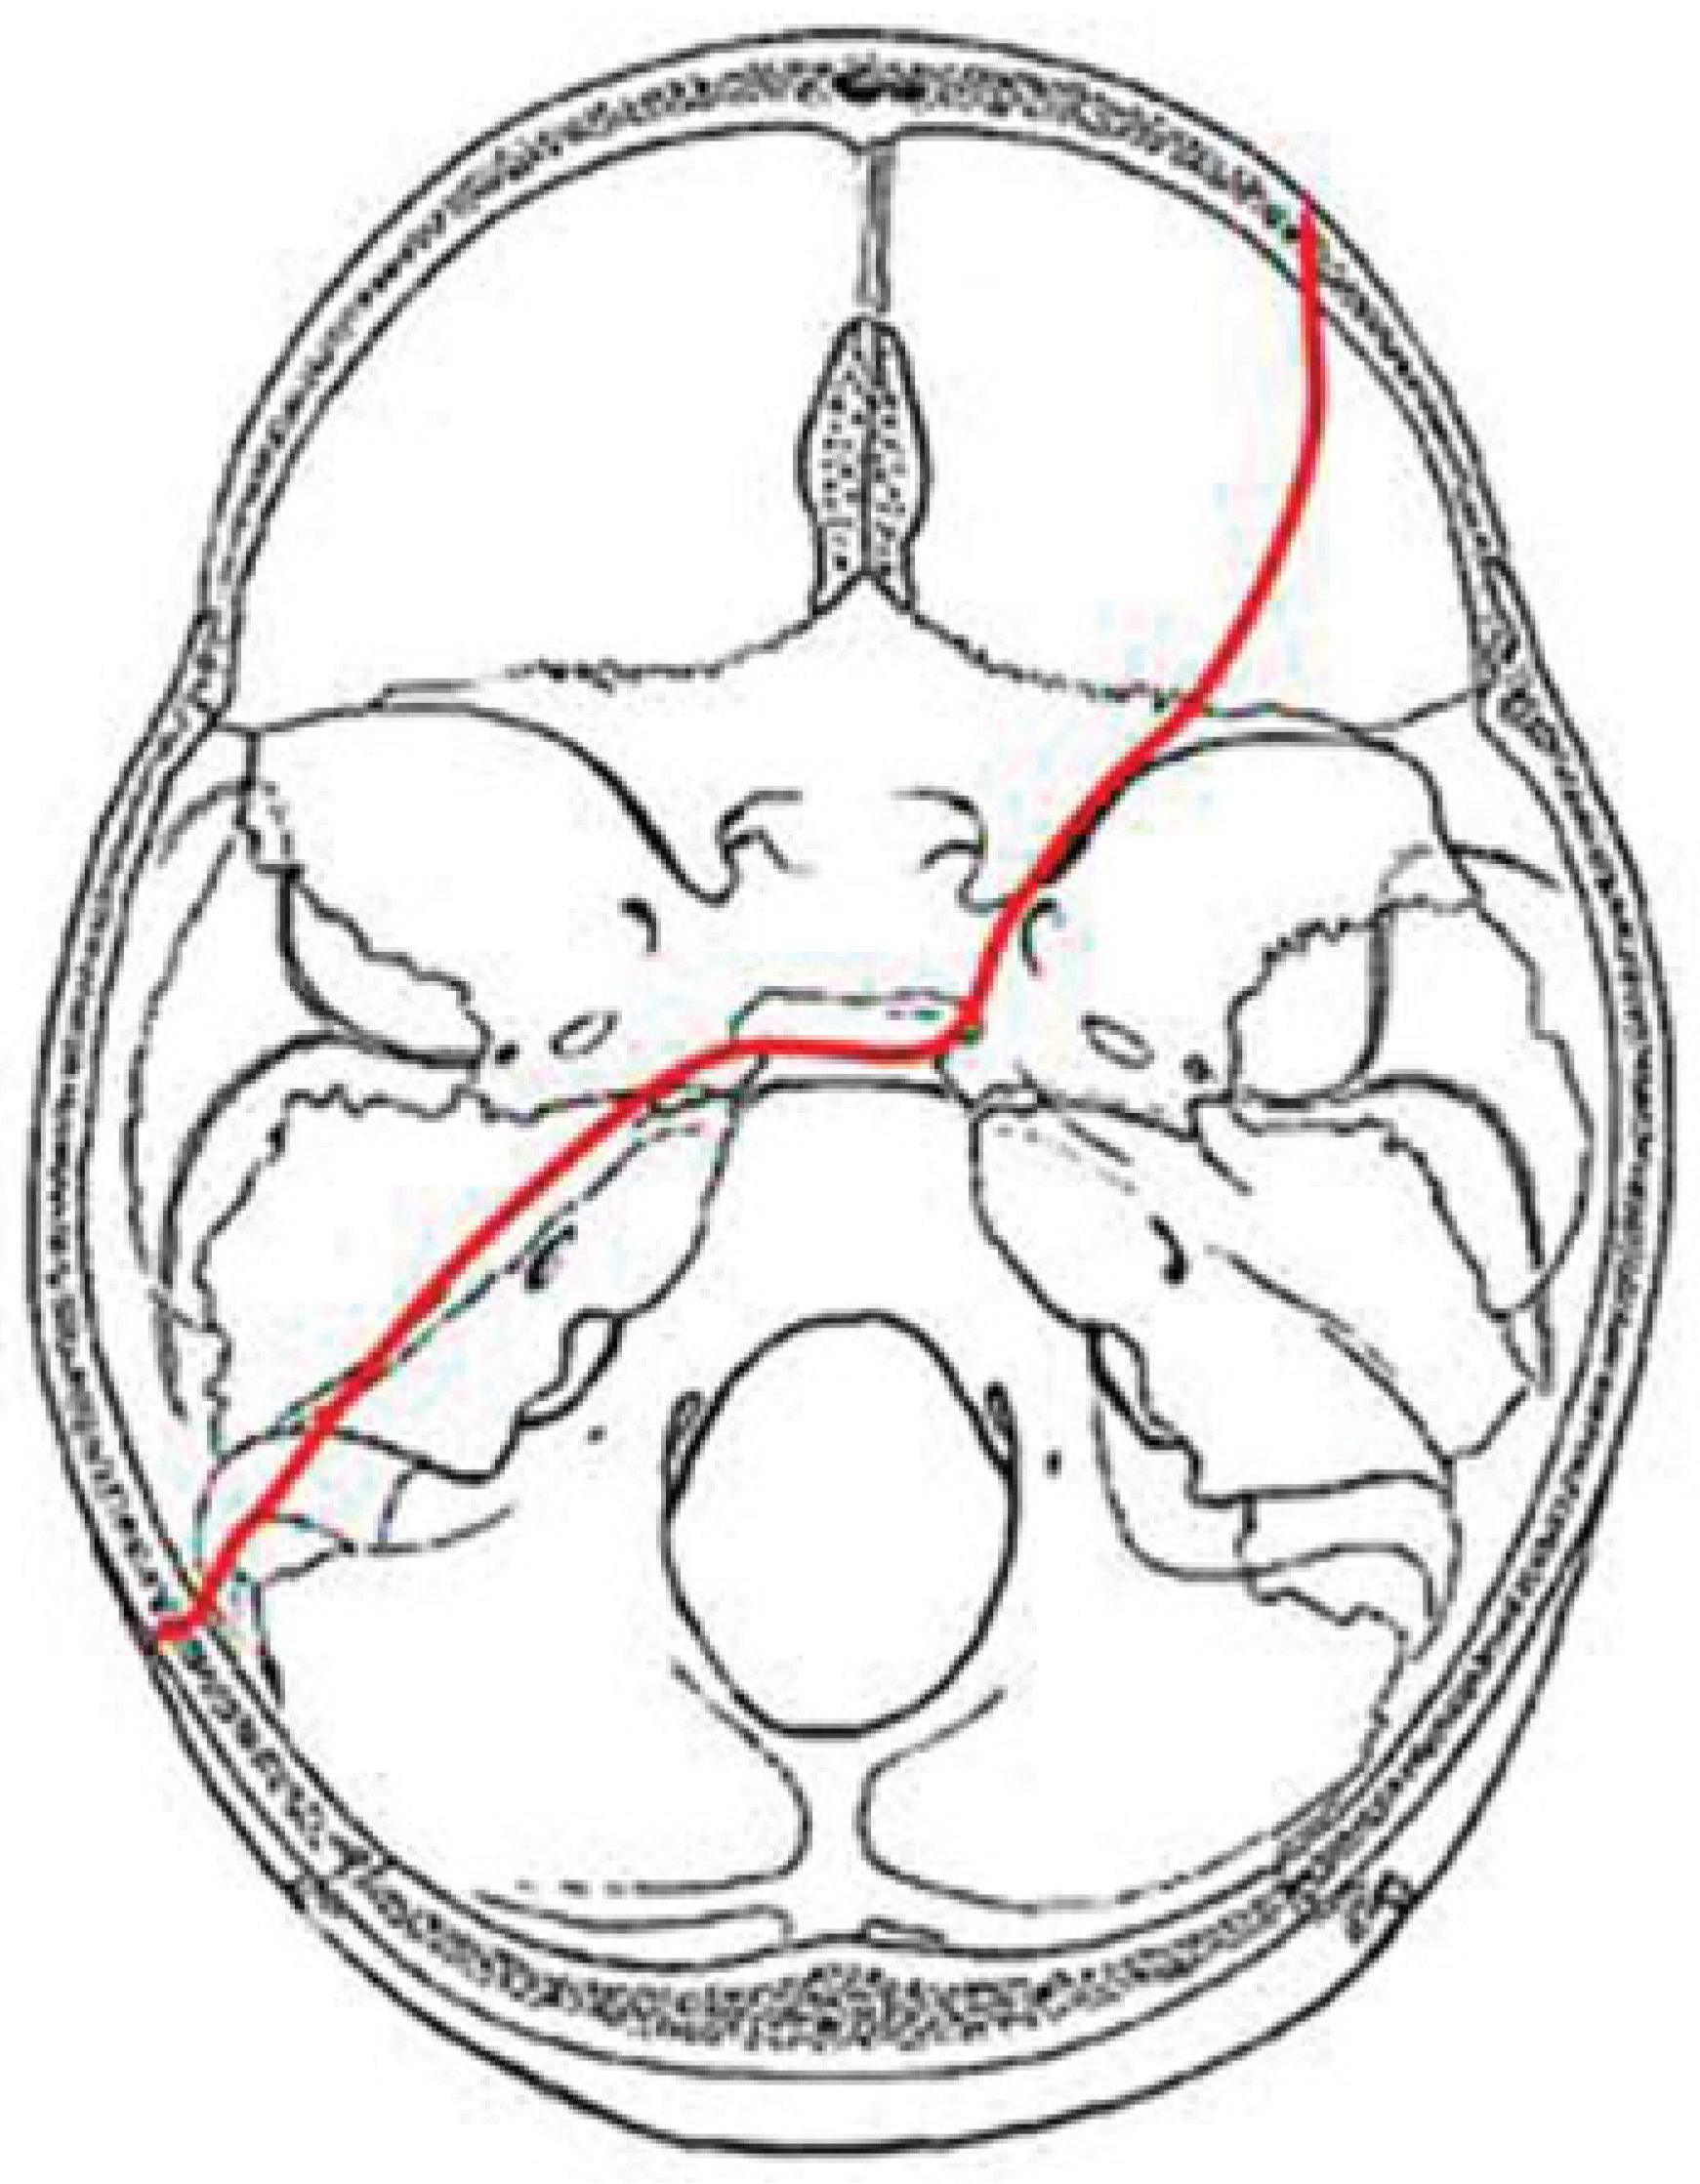

In our study we identified four major fracture patterns of transsphenoidal basilar skull fractures, which were: anterior transverse (AT), lateral frontal diagonal (LFD), posterior trans-verse (PT), and mastoid diagonal (MD), which matches Clark’s descriptions of the transsphenoidal basilar skull fractures.17

AT Pattern

The key to the identification of the AT pattern is the demon-stration of a coronal fracture through the sphenoidal plane at the base of the anterior clinoid processes. The exact position across the anterior sphenoid body varies slightly from the sphenoidal limbus to the roof of the extreme posterior ethmoid air cells. Most fractures pass through the roof of the sphenoid sinus anteriorly. The fracture typically begins in the squamous portion of the temporal bone, courses anteriorly to the sphenotemporal buttress, and then proceeds medially along the orbital surface (vertical plate) or the anterior cerebral surface (horizontal plate) of the sphenoid bone. The fracture intersects the sphenoid body at or slightly posterior to the junction, with the ethmoid bone producing the characteristic transverse fracture across the posterior aspect of the floor of the anterior cranial fossa. The fracture exits the sphenoid body through a similar pathway involving the contralateral greater wing along the orbital surface (horizontal plate) or the anterior cerebral surface (vertical plate). In severe fractures, the fracture will continue to propagate into the contralateral squamous portion of the temporal bone (Figure 5).

Figure 5. Composite drawing of the anterior transverse fracture pattern (left impact).